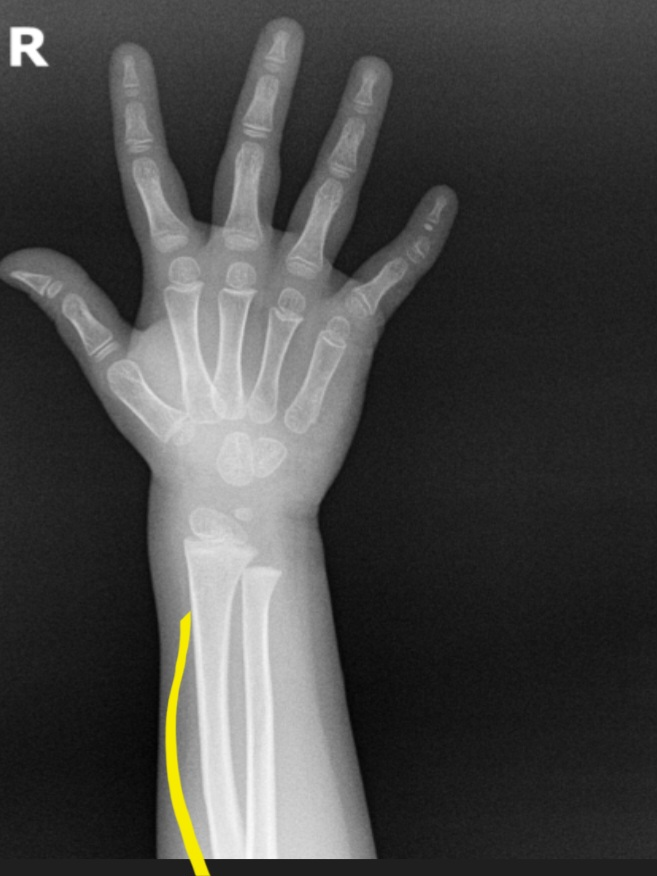

사진에 보이는 저뼈가 약간 곡선인데 맞나요??

사진은 네이버에서 아기 팔엑스레이 치면 나오는 사진입니다.

해당 부위는 요골이라는 뼈로, 일반적으로 약간의 곡선 형태를 띄는 경우가 많은 뼈입니다. 크게 걱정하지 않으셔도 될 것으로 보입니다.

• 네, 뼈가 완전히 직선이지 않습니다. 정상적으로 약간 곡선으로 되어 있는 것이 맞습니다. 병원에서 정상이라고 하였다면 크게 걱정하지 않으셔도 무방합니다.

아기와 성인의 팔 뼈는 자연스럽게 약간 곡선 형태를 가지고 있어 정상입니다. 특히 어린 아기의 뼈는 성장하면서 조금 더 굽거나 변형된 것처럼 보일 수 있지만 이는 정상 범위입니다 사진 속 곡선도 정상적인 모양이고 크게 걱정하지 않으셔도 됩니다. 궁금하시면 소아과나 소아 정형외과 한번 더 확인 받으셔도 좋아요!